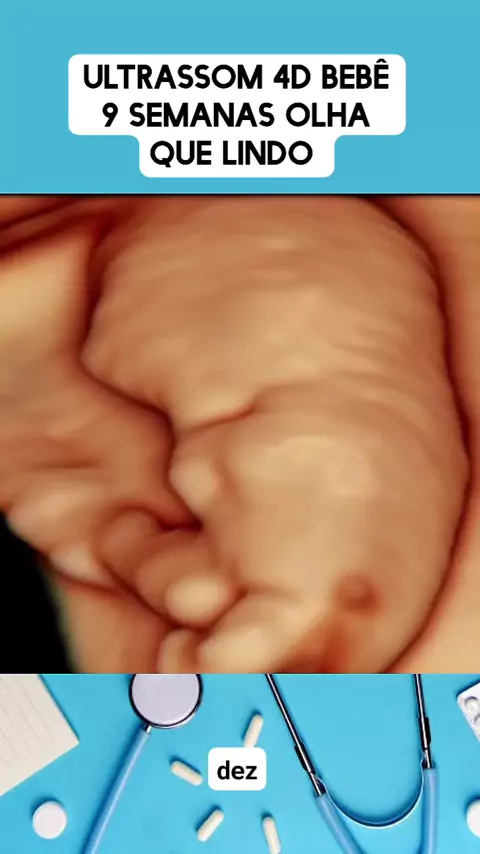

ultrassom 4d 9 semanas #medico #medicina #Saúde #viraliza